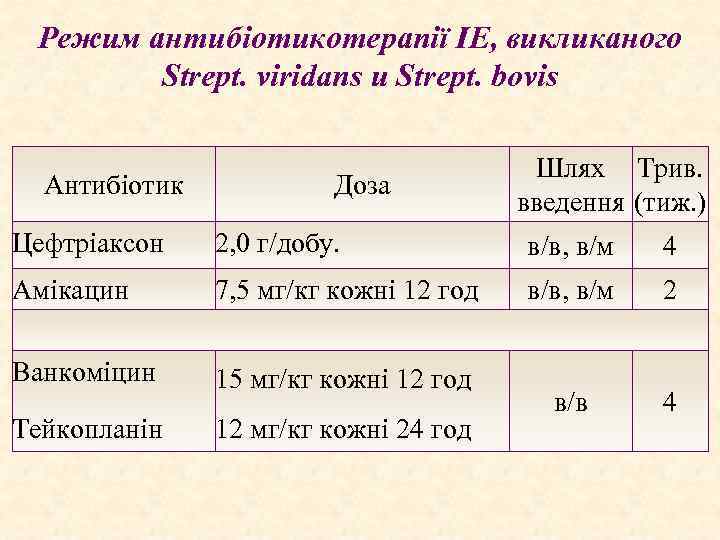

Режим антибіотикотерапії ІЕ, викликаного Strept. viridans и Strept. bovis Антибіотик Доза Шлях Трив. введення (тиж. ) Цефтріаксон 2, 0 г/добу. в/в, в/м 4 Амікацин 7, 5 мг/кг кожні 12 год в/в, в/м 2 Ванкоміцин 15 мг/кг кожні 12 год Тейкопланін 12 мг/кг кожні 24 год в/в 4